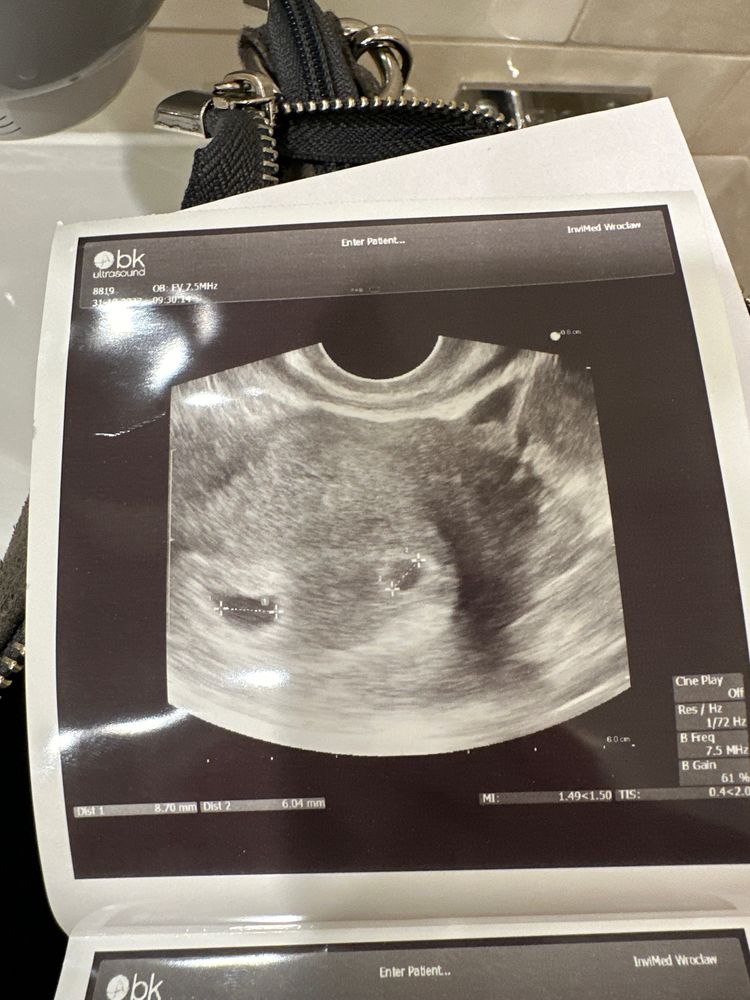

УЗИ на 22 дпп

ДВ всем. На 20 дпп хгч был 29 600. Сегодня 22дпп была на первом УЗИ. В матке 2 пя,эмбрионов нет,про жм и размеры пя врач не сказала. Теперь я загналась,что они пустые. У многих на этом сроке жм есть,а у кого-то уже и эмбрион. На следующее УЗИ только 4 числа.

P.s. Нашла в описании размеры пя 10 и 12 мм

Вроде в левом что-то виднеется. Вы когда на узи теперь? Жм по идее уже есть или вот-вот должны появиться.

Анна, вот мне тоже кажется,что в том,которое поменьше я вижу жм. На УЗИ 04.04 получается на 31 дпп

У меня на фото, кстати, практически тоже самое было на 19 дпп

Еще рано. Эмбрионы должны появится где то при размере плодного яйца около 20 мм..

Если совсем невтерпеж, то сходите на узи на 25 дпп. У меня с 2 трехдневками на 25 дпп уже пульсация сердечек была…на 19, кстати, еще эмбрионов не было видно) удачи Вам)